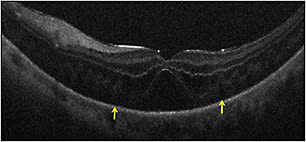

In the PIONEER study, macular indications for surgery, such as macular hole (23%) and ERM (35%), were most common. Retinal detachment and proliferative diabetic retinopathy were also frequent indications for surgery. In membrane peeling cases, iOCT successfully demonstrated completion of peel or residual membranes (Figure 2).

Figure 2. Intraoperative OCT and macular holes. (Top) Preincision intraoperative OCT B-scan revealing full-thickness macular hole (red asterisk). (Bottom) Postpeel intraoperative OCT B-scan revealing expansion of the subretinal hyporeflectivity band between the photoreceptor layers and the retinal pigment epithelium (yellow arrows).

In macular hole cases, alterations in hole geometry were noted, and increased hyporeflectivity in the subretinal space was demonstrated, similar to previous studies.1,4,6 Partially peeled internal limiting membrane was often identified as a curled, hyperreflective, thin band on the B-scan.1,6